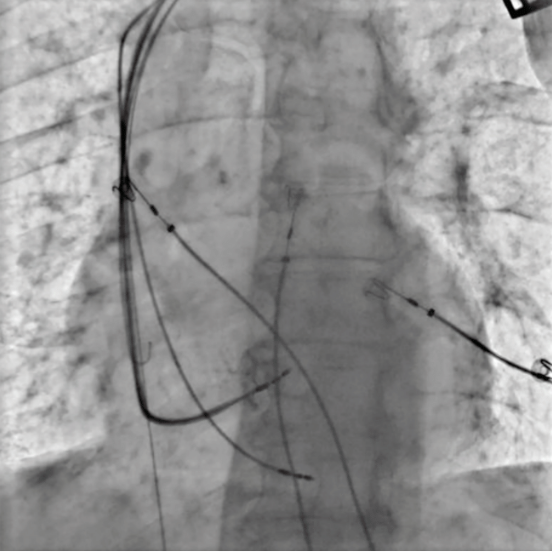

After obtaining both verbal and written consent, the patient was taken to the laboratory. The device therapy was turned off and the mode was changed to DOO. A venogram was performed and showed vein patency. Two axillary venous access were obtained. The Selectra 65/39 delivery sheath (Biotronik) was used to engage the septum. A Solia S 60-cm lead (Biotronik) was prepared for septal penetration. A good septal spot was found and the lead penetrated towards the LV septum (Video 1). Although unipolar pacing showed a right bundle branch block pattern and stable lead parameter, the V5-R Wave Peak Time (RWPT) was too long (140 ms) (Figure 2A). Therefore, we opted to implant an LV lead as well. The coronary sinus (CS) was engaged and good lateral branch was observed. A quadripolar LV lead was placed into the lateral branch (Video 2). Lead parameters were stable with no evidence of phrenic nerve stimulation. Both the Selectra sheath and CS sheaths slitted with no evidence of lead dislodgements. Leads attached to the device (Intica Neo 5 HF-T, Biotronik). The device was programmed as DDD @50 bpm, LV>RV offset of 20 ms, and atrioventricular delay (AVD) of 120 ms (Figure 2B). The final paced QRS duration was 126 ms (Figure 1B). The patient was discharged same day and no acute complication was noted.